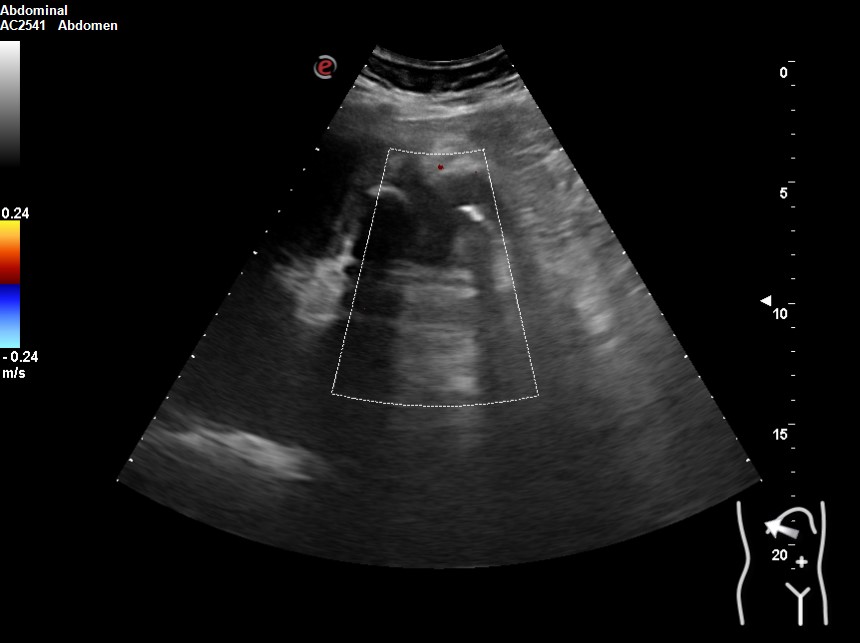

Hallazgos ecográficos

Vesícula biliar desestructurada, de paredes mal definidas con litiasis de 20 mm, que contacta con la pared de la segunda porción duodenal. Porta de tamaño normal. Vía biliar no dilatada.

En los análisis destacaban: GOT 419 GPT 525 FA 373 Bilirrubina 5,3 PCR 184 19.800 leucocitos con neutrofilia. Se realiza tomografía computarizada y nueva ecografía. Se inicia antibioterapia e ingresa con impresión diagnóstica de colecistitis sobre colecsitopatía crónica versus neoplasia vesicular.